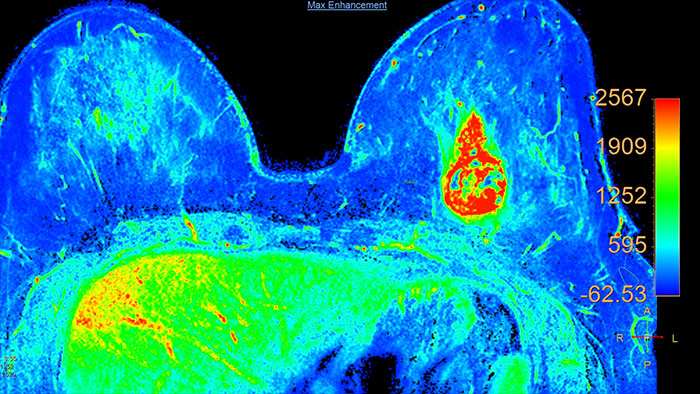

DynaCAD Breast

MR DynaCAD Breast*

Next generation of breast care

Tailored to enhance the review and analysis of MRI breast studies by providing a flexible workspace with custom hanging protocols and multi-vendor** viewing capabilities. DynaCAD’s automatic segmentation allows on-the-fly user modification and provides volume analysis, lesion composition statistics, histograms, and a 3D rendered morphological overview.

Benefits

• Results are automatically incorporated into standardized reports.

• The DynaLOC Breast Interventional Planning software module offers visual guidance for planning MR-guided breast biopsy procedures.